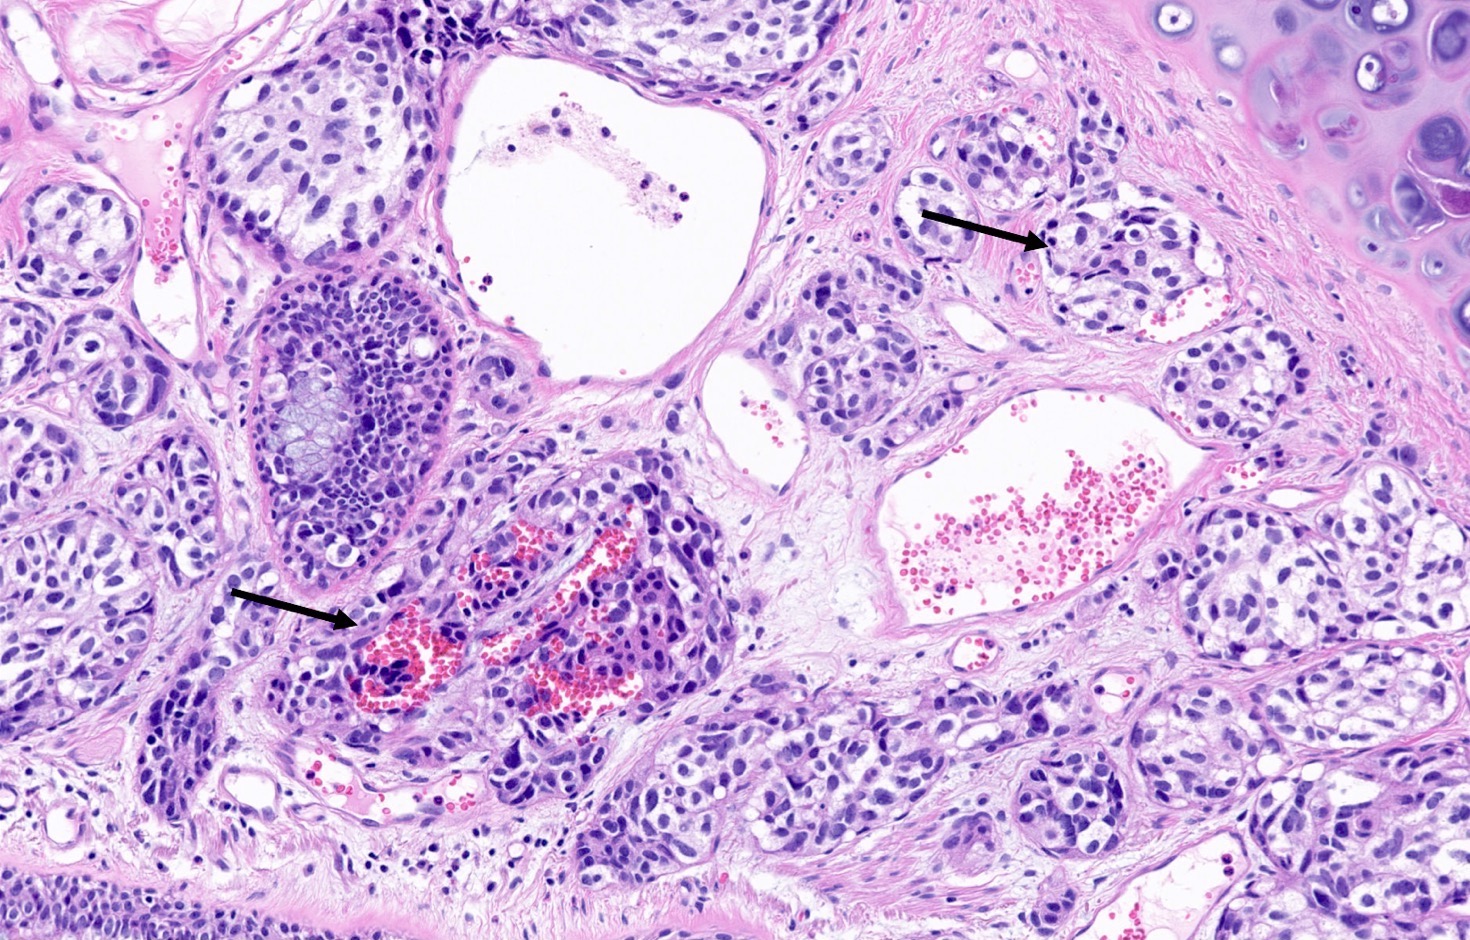

Microscopic (histologic) description

- Diagnostic criteria

- Neuroendocrine tumor with size ≥ 5 mm with < 2 mitoses/2 mm2 and absence of necrosis

- Neuroendocrine growth pattern (organoid, trabecular, rosette formation, nested) or pseudoglandular, follicular and papillary growth

- Tumor cells are uniform with a polygonal shape, round to oval nuclei with salt and pepper chromatin as well as inconspicuous nucleoli and moderate to abundant eosinophilic cytoplasm

- Spindle cells and clear cell features can be seen

- Stroma is fine and highly vascularized; hyalinization, cartilage or bone formation are possible

Microscopic (histologic) images

Contributed by Philippe Joubert, M.D., Ph.D., Jijgee Munkhdelger, M.D., Ph.D. and Andrey Bychkov, M.D., Ph.D.